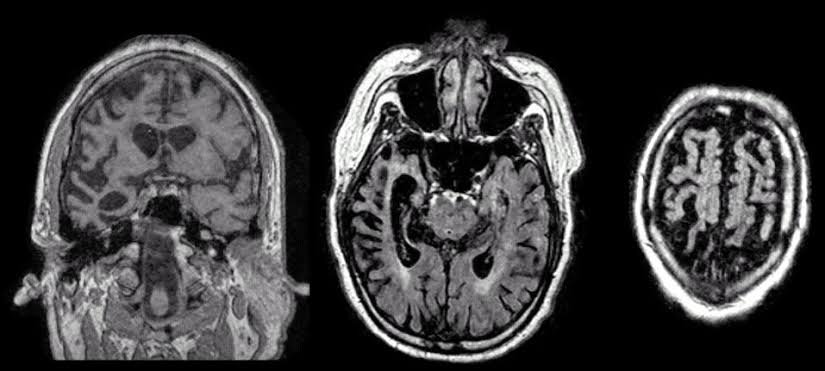

VEN’lerin çeşitli nöropsikiyatrik hastalıklarda rol aldığı bilinmektedir. Özellikle fronto-temporal demansın (bunama) başlangıç aşamalarında VEN’ler saldırıya uğrar. Fronto-temporal demans, beynin en çok VEN barındıran bölgelerinde meydana geldiği için bu zihinsel bozuklukta empati, sosyal farkındalık ve öz kontrol devre dışı kalır. Burada ön singulatta yer alan VEN’lerin %74’ü yok olmuştur ve kalan VEN’ler de çoğunlukla işlevsizdir.

Fronto-temporal demans normal demans aksine genç yaşlarda ortaya çıkabilmekte ve zamanla hastalık tablosu kötüleşmektedir. 50'li, 60'li ve hatta 20'li yaşlarda veya 80'li yaşların sonlarında gelişmeye başlayabilmektedir. Alzheimerdan farklı olarak hafıza yitiminden ziyade, frontal ve temporal lobda gerçekleşen fonksiyon kaybı sonucu dil işlevinde azalma ve davranış bozuklukları ile karakterizedir. Bu bölgelerde ölen nöronlar, çoğunlukla VEN'ler yıllar geçtikçe kötüleşen bir demans tablosuna neden olmaktadır. Fronto-temporal demans VEN'ler dışındaki komşu nöronları genellikle etkilememektedir. Hastalığın yalnızca VEN'leri hedef aldığını ve bu yüzden bireyin sosyal fonksiyonlarında büyük kayıplar yaşandığı düşünülmektedir.